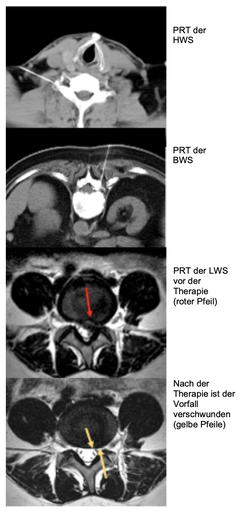

Periradikuläre Therapie (PRT)

Die heute am häufigste angewandte Behandlung von Bandscheibenvorfällen und Spinalkanalstenosen wurde vor fast 40 Jahren von Prof. Rainer Seibel erfunden und weltweit zuerst eingesetzt. Durch mehrfache präzise Injektionen von örtlich wirksamen Kortison und zusätzlichen Substanzen können nicht nur Schmerzen behoben, sondern auch Fehlfunktionen therapiert werden. Zusätzlich werden etwa 60% der behandelten Bandscheibenvorfälle kleiner oder verschwinden vollständig (siehe mittlere Spalte).

Die verabreichte Kortisonmenge ist gering, wirkt zu 97% am Injektionsort und wird dort in 3 Wochen resorbiert.

Nebenwirkungen sind deshalb selten.

Durch die verabreichte Lokalanästhesie ist der Eingriff praktisch schmerzfrei.